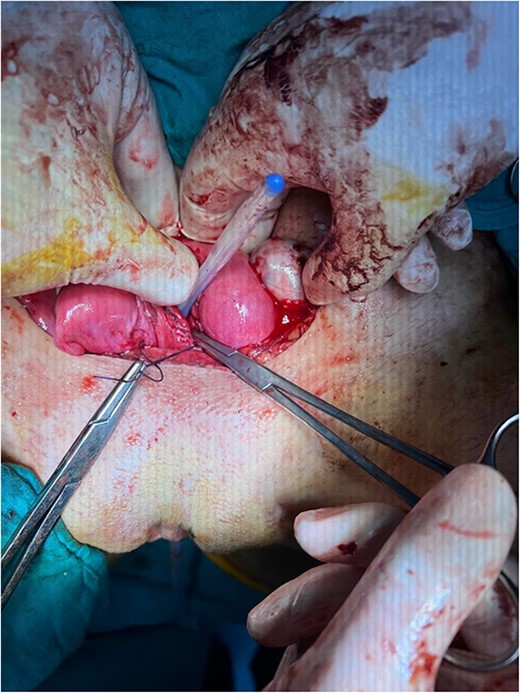

The vaginal diaphragm was removed, the edges were sutured to reduce recurrence, and a silicone catheter was placed trans-vaginally to reduce diaphragm recurrence and ensure adequate hematoma drainage (Fig. 5). The surgical incision was sutured across the abdomen, and the abdomen was closed. The post-operation recovery was uneventful, and the patient was discharged three days later.

The silicon catheter placed trans-vaginally to reduce diaphragm recurrence and ensure adequate hematoma drainage.